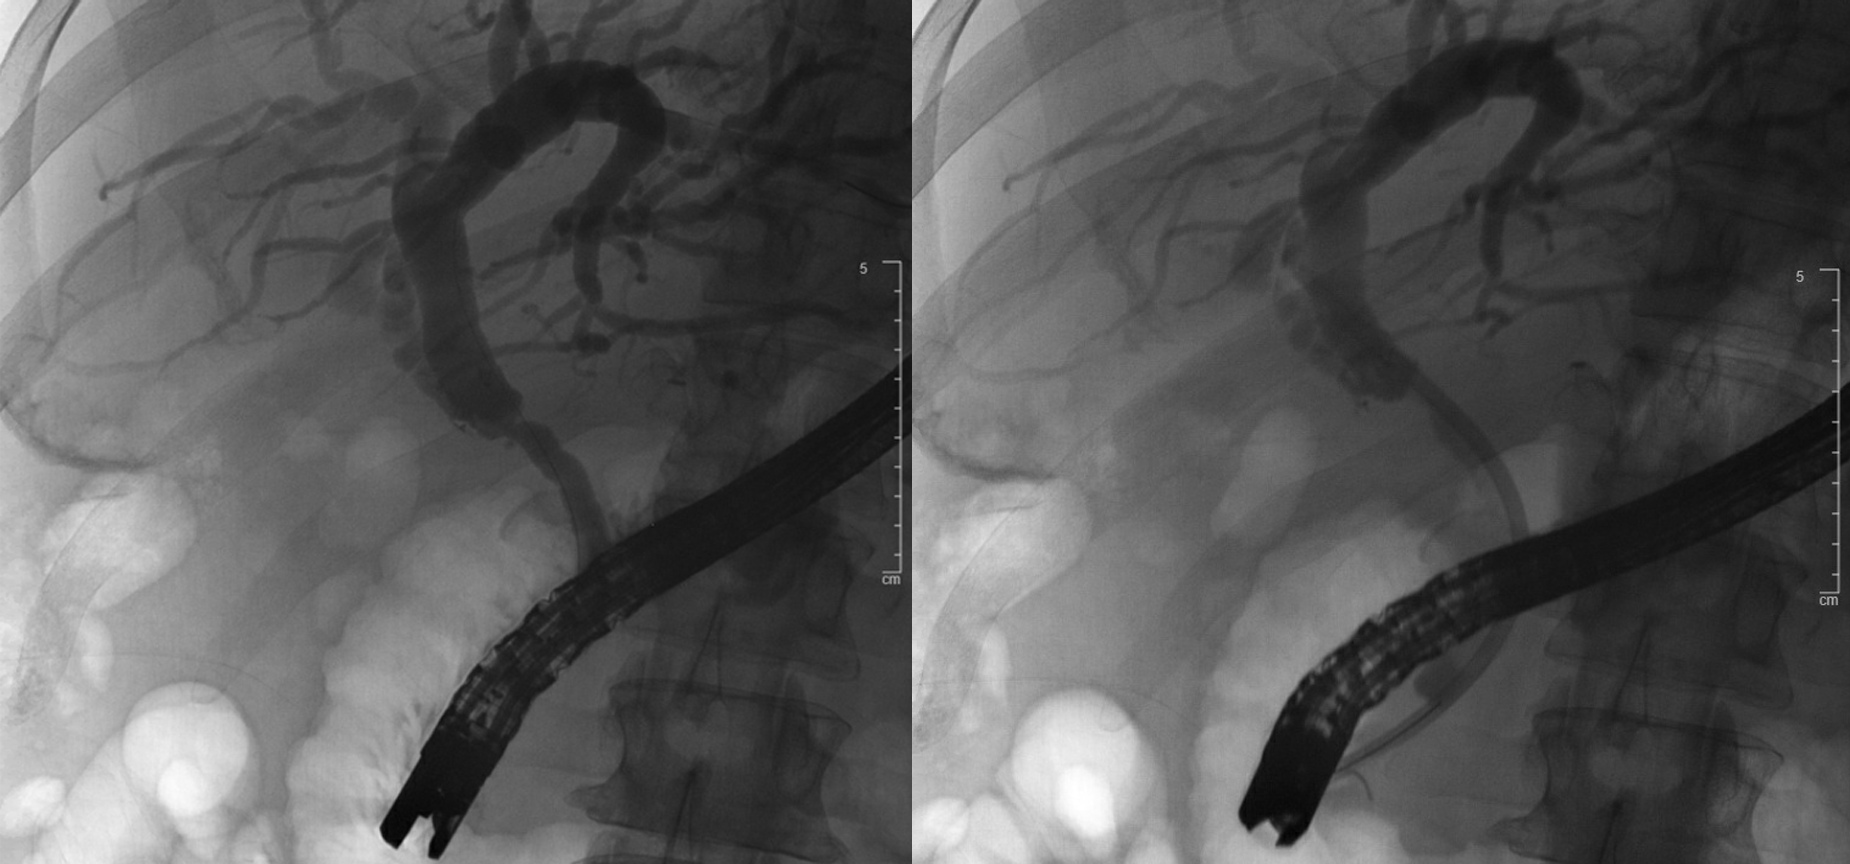

The patient undergoes ERCP which revealed an anastomotic stricture as shown in Figure 3 that was dilated to 6mm and stented with a 10 Fr plastic stent.

Figure 3: Cholangiogram demonstrating anastomotic biliary stricture (left) and post- stent placement (right)